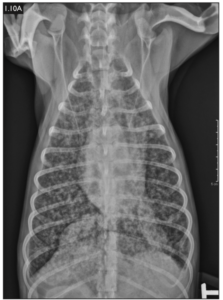

Image of thoracic radiograph of a dog with lungs heavily infected with blasto (from Weese and Evason, Infectious Diseases of the Dog and Cat, A Colour Handbook).